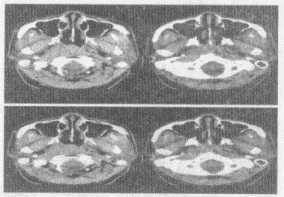

男,52岁,右耳鸣2个月余,伴鼻塞,CT如图所示,最可能的诊断是()

A . 鼻咽淋巴瘤

B . 鼻咽纤维血管瘤

C . 增殖体肥大

D . 鼻咽癌

E . 鼻咽部慢性炎症